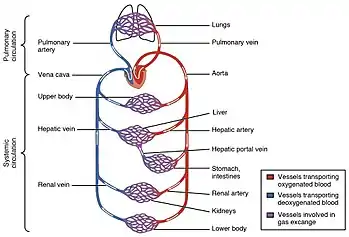

The circulatory system includes the heart, blood vessels, and blood.[2] The cardiovascular system in all vertebrates, consists of the heart and blood vessels. The circulatory system is further divided into two major circuits – a pulmonary circulation, and a systemic circulation.[8][1][3] The pulmonary circulation is a circuit loop from the right heart taking deoxygenated blood to the lungs where it is oxygenated and returned to the left heart. The systemic circulation is a circuit loop that delivers oxygenated blood from the left heart to the rest of the body, and returns deoxygenated blood back to the right heart via large veins known as the venae cavae. The systemic circulation can also be defined as two parts – a macrocirculation and a microcirculation. An average adult contains five to six quarts (roughly 4.7 to 5.7 liters) of blood, accounting for approximately 7% of their total body weight.[9] Blood consists of plasma, red blood cells, white blood cells, and platelets. The digestive system also works with the circulatory system to provide the nutrients the system needs to keep the heart pumping.[10]

The pulmonary circulation is the part of the circulatory system in which oxygen-depleted blood is pumped away from the heart, via the pulmonary artery, to the lungs and returned, oxygenated, to the heart via the pulmonary vein.

Oxygen-deprived blood from the superior and inferior vena cava enters the right atrium of the heart and flows through the tricuspid valve (right atrioventricular valve) into the right ventricle, from which it is then pumped through the pulmonary semilunar valve into the pulmonary artery to the lungs. Gas exchange occurs in the lungs, whereby CO2 is released from the blood, and oxygen is absorbed. The pulmonary vein returns the now oxygen-rich blood to the left atrium.[10]

Systemic circulation

The systemic circulation is a circuit loop that delivers oxygenated blood from the left heart to the rest of the body through the aorta. Deoxygenated blood is returned in the systemic circulation to the right heart via two large veins, the inferior vena cava and superior vena cava, where it is pumped from the right atrium into the pulmonary circulation for oxygenation. The systemic circulation can also be defined as having two parts – a macrocirculation and a microcirculation.[10]

Portal veins

The general rule is that arteries from the heart branch out into capillaries, which collect into veins leading back to the heart. Portal veins are a slight exception to this. In humans, the only significant example is the hepatic portal vein which combines from capillaries around the gastrointestinal tract where the blood absorbs the various products of digestion; rather than leading directly back to the heart, the hepatic portal vein branches into a second capillary system in the liver.